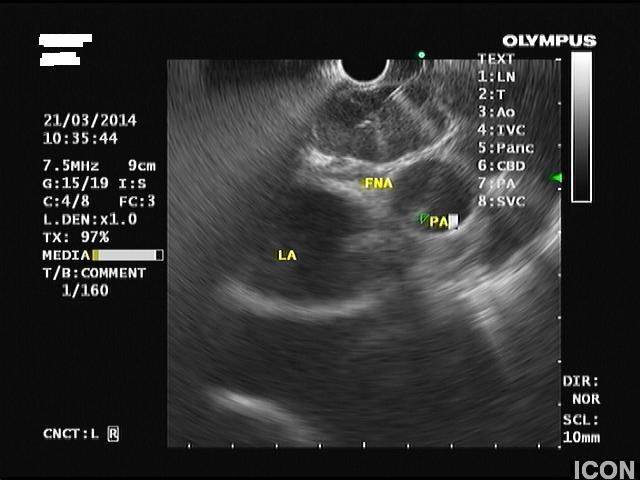

Γυναίκα 58 ετών, υποβλήθηκε προληπτικά σε υπέρηχο άνω κοιλίας όπου διαπιστώθηκε μια κύστη στην κεφαλή του παγκρέατος. Το εύρημα επιβεβαιώθηκε σε μαγνητική τομογραφία (MRI/MRCP) που δεν έδειξε άλλα παθολογικά ευρήματα στο πάγκρεας. Ο ενδοσκοπικός υπέρηχος έδειξε μια δίχωρη κύστη, διαστάσεων 6,5Χ12,5 χιλ, στην παγκρεατική κεφαλή.

Η κύστη είχε επικοινωνία με κλάδο του παγκρεατικού πόρου, ενώ ο μείζων παγκρεατικός πόρος ήταν φυσιολογικής διαμέτρου σε όλη την πορεία του. Επίσης, διαπιστώθηκε δεύτερη κύστη διαμέτρου 2,5χιλ στο σώμα του παγκρέατος που δεν είχε απεικονιστεί στην MRI.

Έγινε βιοψία με λεπτή βελόνα 22g (FNA) και αναρροφήθηκε πλήρως η κύστη της κεφαλής. Οι βιοχημικοί δείκτες του υγρού της κύστης ήταν: CEA 467, αμυλάση 1550.

Τα ευρήματα ήταν συμβατά με ένα ενδοπορικό θηλώδες βλεννώδες νεόπλασμα των κλάδων του πόρου (branch-duct IPMN).

Λήψη υγρού με λεπτή βελόνη (FNA)